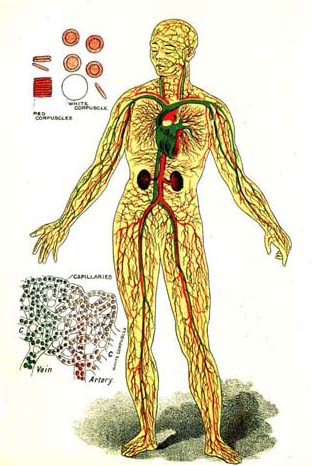

PLATE 1. THE CIRCULATION.

5. The Blood-Vessels.—The tubes through which the blood is carried are called blood-vessels. There are three kinds of blood-vessels. One set carry the blood away from the heart, and are called arteries (ar'-te-ries). Another set return the blood to the heart, and are called veins. The arteries and veins are connected at the ends farthest from the heart by many very small vessels. These minute, hairlike vessels are called capillaries (cap'-il-la-ries).

6. The Arteries.—An artery leads out from the lower chamber of each side of the heart. The one from the right side of the heart carries the blood only to the lungs. The one from the left side of the heart carries blood to every part of the body. It is the largest [Pg 51]artery in the body, and is called the aorta. Soon after it leaves the heart the aorta begins to send out branches to various organs. These divide in the tissues again and again until they become so small that only one corpuscle can pass through at a time, as shown in the colored plate. (Frontispiece.)

7. The Veins.—These very small vessels now begin to unite and form larger ones, the veins. The small veins join to form larger ones, until finally all are gathered into two large veins which empty into the upper chamber of the right side of the heart. The veins which carry blood from the lungs to the heart empty into the upper chamber of the left side of the heart.

8. What is Done in the Blood-Vessels.—While the blood is passing through the small blood-vessels in the various parts of the body, each part takes out just what it needs to build up its own tissues. At the same time, the tissues give in exchange their worn-out or waste matters. The red blood corpuscles in the capillaries give up their oxygen, and the blood receives in its stead a poisonous substance called carbonic-acid gas.

9. Red and Blue Blood.—While in the arteries the blood is of a bright red color; but while it is passing through the capillaries the color [Pg 52]changes to a bluish red or purple color. The red blood is called arterial blood, because it is found in the arteries. The purple blood is called venous blood, because it is found in the veins. The loss of oxygen in the corpuscles causes the change of color.

10. Change of Blood in the Lungs.—Exactly the opposite change occurs in the blood when it passes through the lungs. The blood which has been gathered up from the various parts of the body is dark, impure blood. In the lungs this dark blood is spread out in very minute capillaries and exposed to the air. While passing through the capillaries of the lungs, the blood gives up some of its impurities in exchange for oxygen from the air. The red corpuscles absorb the oxygen and the color of the blood changes from dark purple to bright red again. The purified blood is then carried back to the upper chamber of the left side of the heart through four large veins. The blood is now ready to begin another journey around the body.